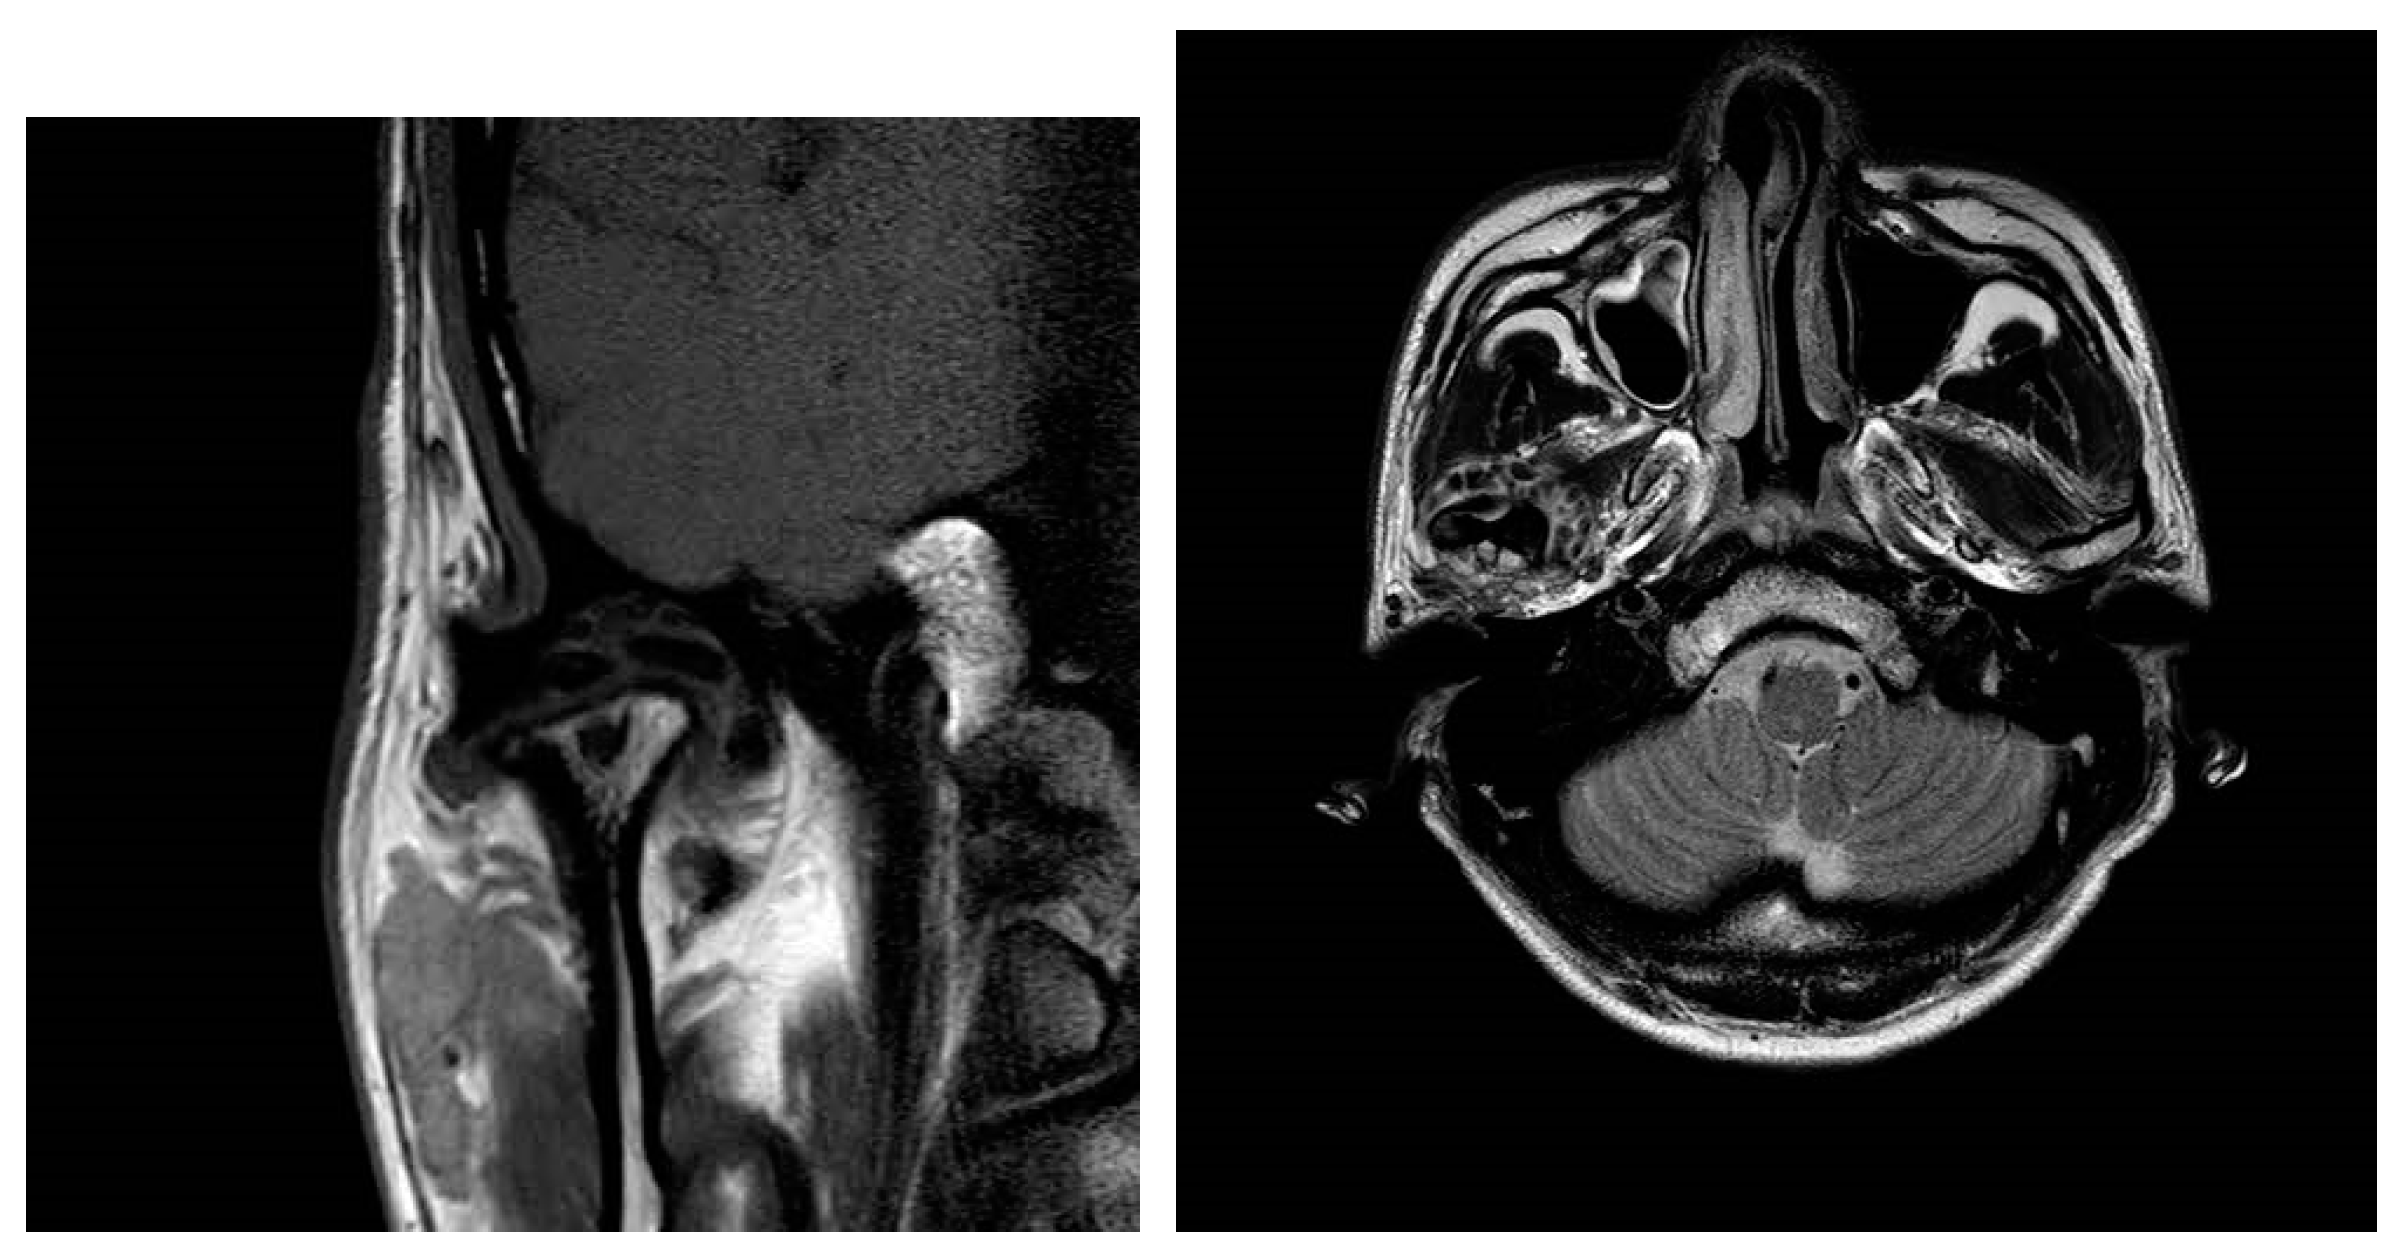

Extensive Synovial Chondromatosis of the Temporomandibular Joint Extending to the Cranial Base